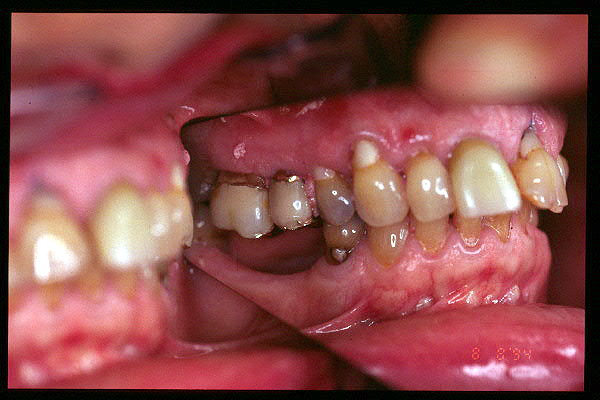

CM Hiperplasia gingival por prótesis

CM Hiperplasia por prótesis